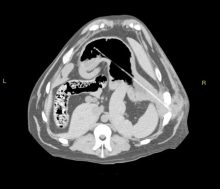

CT And Surgery Of Dog With Recurrent Abcess – Foreign Body

These are CT + intra-operative pictures of a dog who was referred to us with a recurrent abscess over ...